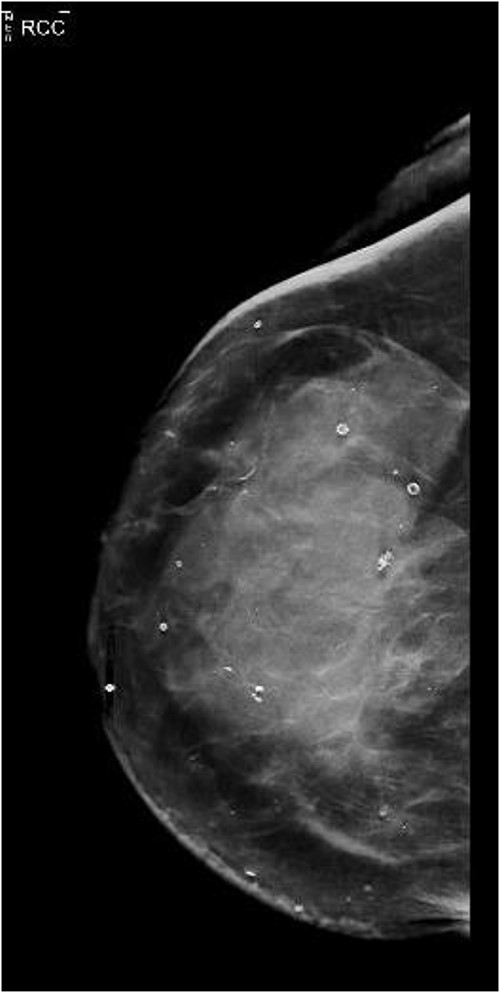

She presented again in 2019 after a fall when she had also complained of bruising in her right breast. The patient had also complained of occasional nausea and abdominal cramping for the past few weeks. A bilateral mammogram was performed on 22 March 2019, which showed dense skin thickening along with medial inferior asymmetry (Fig. 1). US breast was obtained, and a core needle biopsy was done, which showed invasive lobular carcinoma, T3N1M1, estrogen receptor (ER) positive, progesterone receptor (PR) negative, HER2neu negative.